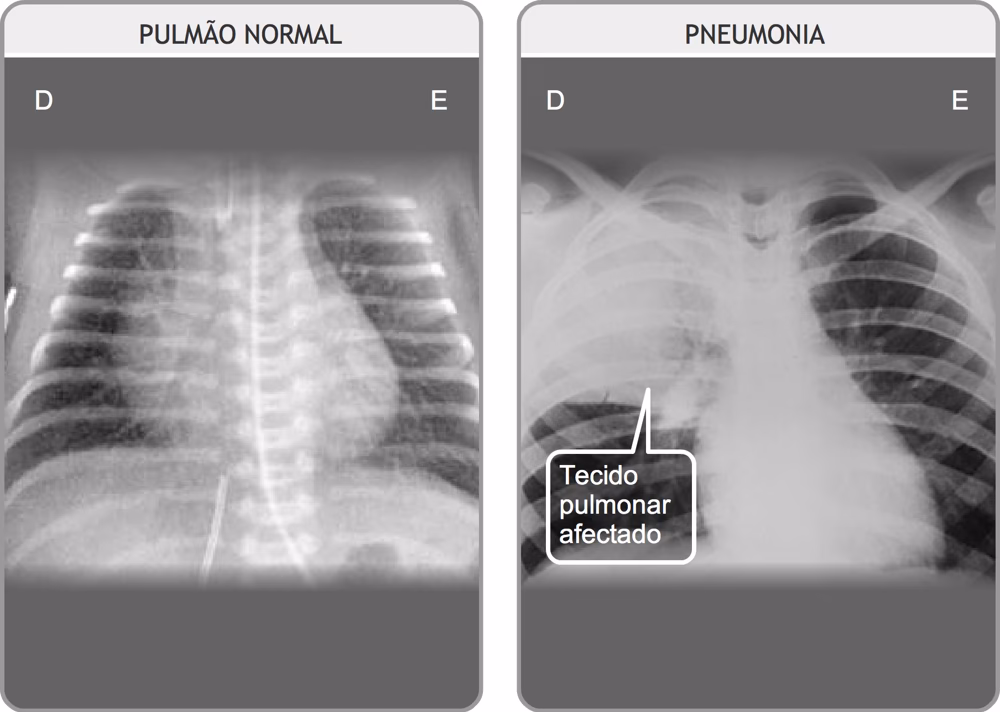

Lungebetændelse er en infektion, der forårsager betændelse i luftsækkene (alveolerne) i den ene eller begge lunger. Når en person har lungebetændelse, kan disse luftsække fyldes med væske eller pus, hvilket gør det svært at trække vejret. Sygdommen kan variere i sværhedsgrad fra mild til livstruende. Man skelner typisk mellem to hovedtyper baseret på, hvor infektionen er erhvervet:

- Bronkitis er en betændelse i de større luftveje (bronkierne), mens lungebetændelse er en infektion dybere nede i selve lungevævet (alveolerne). Lungebetændelse er generelt en mere alvorlig tilstand og giver ofte højere feber og mere udtalt påvirkning af almentilstanden.